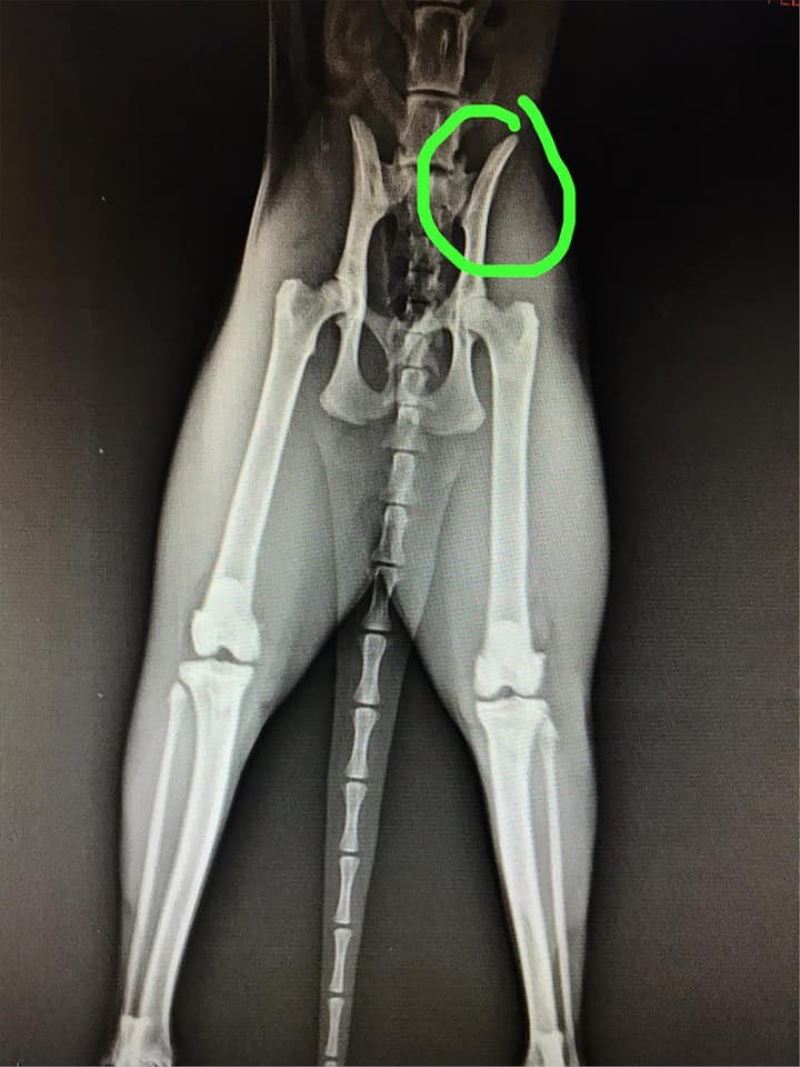

“Kedinin bacağında çatlak var”

Konuyla ilgili konuşan Eskişehir Hayvanları Koruma Derneği Başkanı Gülçin Yapıcı, kedinin kurtarıldığını söyledi. Yapıcı, "Kedimizin bacağında çatlağı varmış. Kedinin tedavisini de yaptırmışlar ve şükür artık güvende. Dernek olarak da şikayette bulunduk. Polis ekipleri şahsı yakaladı ve adli işlemlere başlandı” dedi.